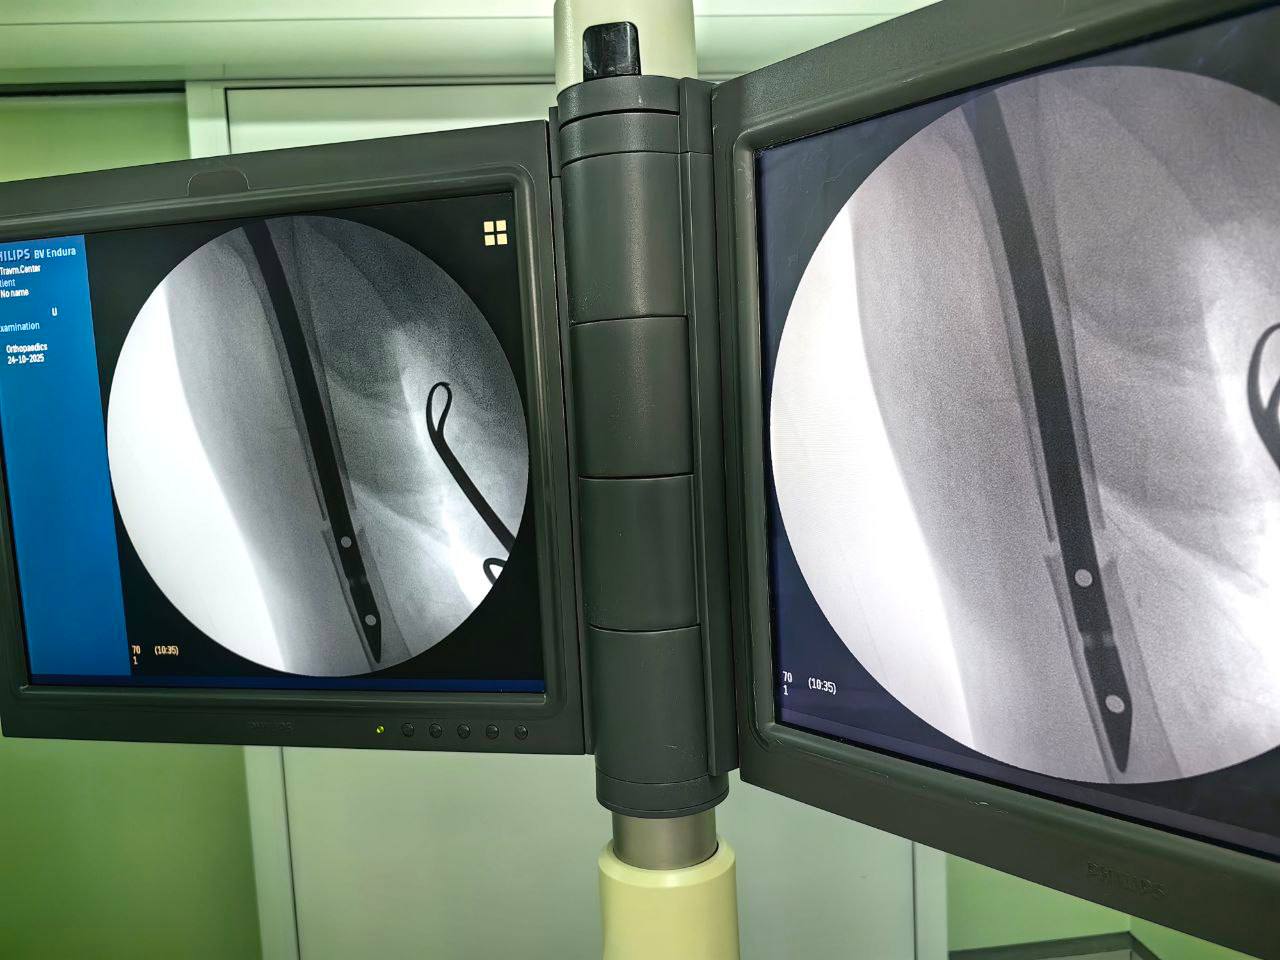

Пациентка поступила с нестабильным диафизарным переломом — травмой, особенно опасной в преклонном возрасте. Чтобы избежать осложнений, врачи решили провести малоинвазивную операцию — интрамедуллярный остеосинтез. В кость установили металлический штифт, который надёжно фиксирует место перелома и позволяет быстрее восстановить подвижность руки.